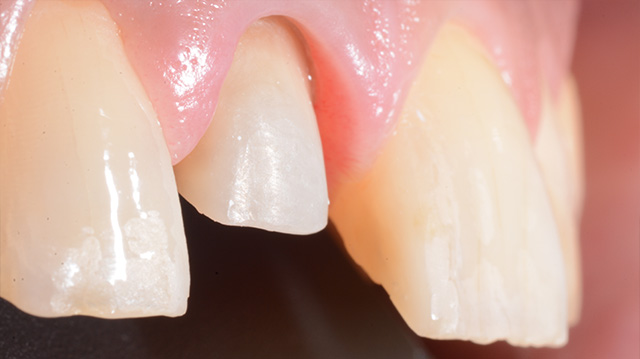

| 年代・性別 | 40代 女性 |

|---|---|

| 主訴 | 右上の犬歯の色が気になる |

| 治療回数 | 3回 |

| 治療期間 | 約1ヶ月 |

| 費用 | 仮歯 5,500円 ジルコニアクラウン 176,000円 |

*キャンセルポリシーをご一読のうえご予約ください